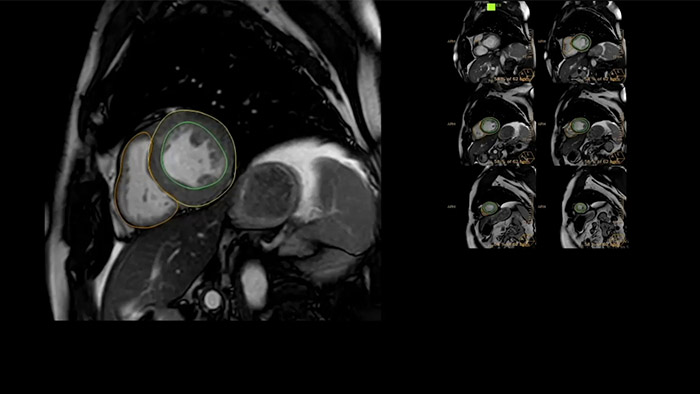

Accelerate workflow for your cardiac exams

IntelliSpace Portal offers a Comprehensive Cardiac MRI Suite, providing dedicated workflows for functional analysis, viability, LGE, cardiac mapping assessment and RV/LV functional analysis in less than 5 min. per case1.

Visualize and evaluate blood flow

Visualise and evaluate blood flow

IntelliSpace Portal MR Caas5,6 4D Flow post-processing solution enables generation of 3D volume reconstructions, to visualise and evaluate blood flow in cardiovascular structures, including heart valves, chambers, and vessels, based on cardiovascular MR 4D Flow imaging.